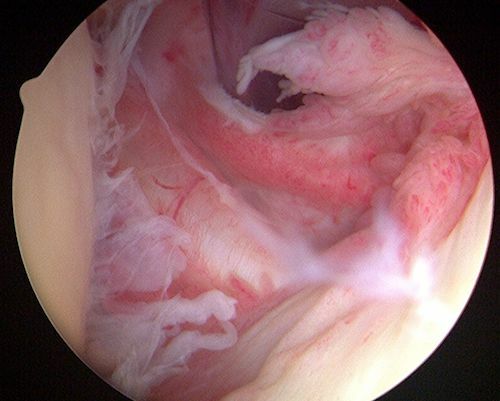

Σε περίπτωση που η συντηρητική θεραπεία δεν προσφέρει τα επιθυμητά αποτελέσματα, το επόμενο βήμα περιλαμβάνει την χειρουργική θεραπεία, με αρθροσκόπηση ώμου. Η αρθροσκόπηση ώμου γίνεται με 3 μικρές οπές 4 χιλιοστών γύρω από τον ώμο, μέσω των οποίων ο χειρουργός εισάγει μια κάμερα και διάφορα εργαλεία.

Κατά την αρθροσκόπηση ώμου, πραγματοποιείται χειρουργικός καθαρισμός της φλεγμονής του ώμου και λείανση του ακρωμίου προκειμένου να αυξηθεί ο διαθέσιμος χώρος για τους τένοντες του ώμου και να αποφευχθεί η τριβή. Στην συνέχεια, ο κ. Παναγόπουλος θα επιδιορθώσει τυχόν ρήξεις τένοντα με τη βοήθεια ειδικών ραμμάτων (άγκυρες).